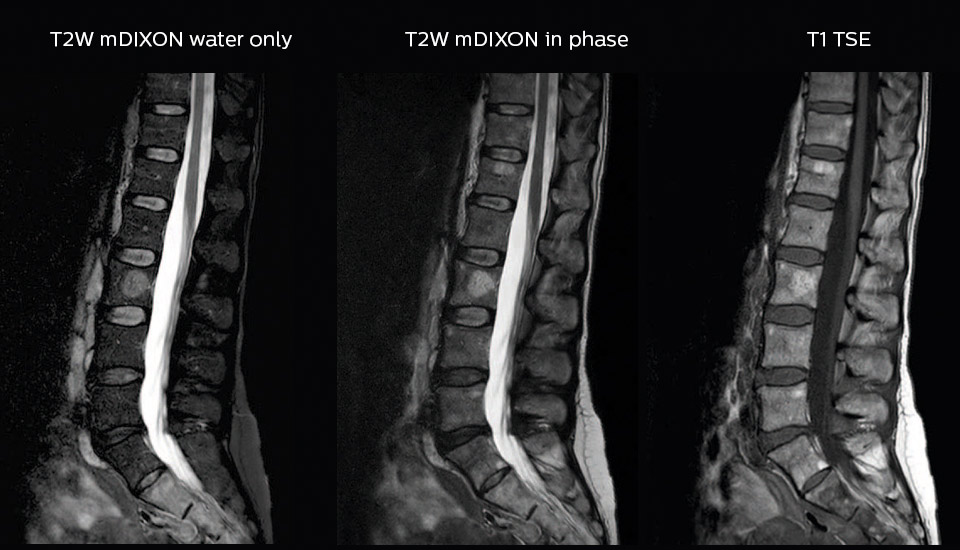

More information without extending time slot

“In our lumbar spine MRI, the value of mDIXON TSE is so obvious. Normally we perform T1 and T2 scans in sagittal and transverse orientation.It used to take too much time to add a sagittal T2 with good fat suppression.But now, using mDIXON TSE, we get the sagittal T2 fat suppressed images ‘for free’, that is: without adding time.”

“Diagnostically that is a great benefit. I sometimes see abnormalities in the fat suppressed sagittal T2 that would be quite challenging to notice in the T2 without fat suppression. There have been several diagnoses that I could make easier because of our exam setup with mDIXON TSE, such as sacrum insufficiency fractures and sacroileitis; these were more challenging with our previous exam setup.”